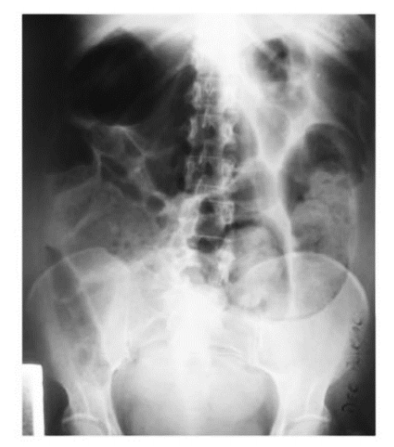

Foi realizado um raio-X de abdome agudo (figura 01) como exame de imagem, que mostrou distensão sem sinais de obstrução mecânica; grande dilatação de ceco e transverso. Além disso, não é visível obstrução mecânica (padrão íleo adinâmico).

FIGURA 1 - Raio-X de abdômen AP em decúbito dorsal